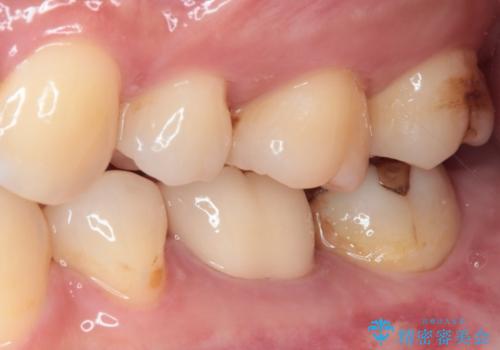

目立つ銀歯をオールセラミッククラウンで自然に|20代女性の審美補綴症例

患者様は根管治療のやり替えは希望されなかったため、ファイバーコア+オールセラミッククラウンによる補綴治療を行いました。

精度の高い補綴治療は、

・歯と被せ物のすき間が少ない

・汚れが溜まりにくい

という特徴があり、二次う蝕(被せ物の中で再発する虫歯)のリスクを低減できます。

見た目だけでなく、将来の歯の健康を守ることも大切にした治療を行っています。